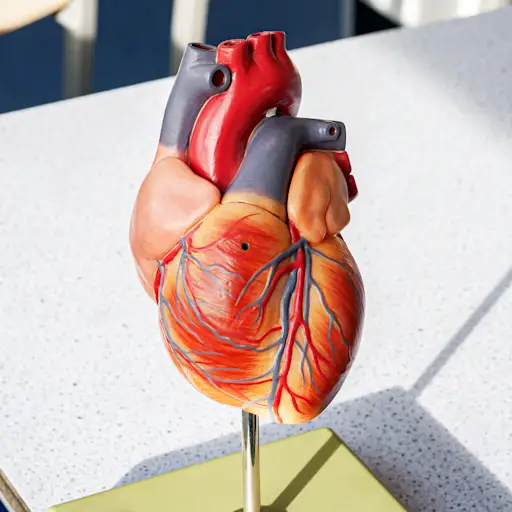

有案子为重命名心力衰竭而制作。图森亚利桑那大学Sarver Heart Center主任Nancy K. Sweitzer博士说,“失败”一词表示最终的最终性,这根本不代表这种情况。并不是说这并不是严重的:毕竟,心力衰竭意味着您的心脏无法抽出其通常的健康血液。随着时间的流逝,循环减少会对人体的所有器官造成损失。但是与心脏病发作不同,它并非一次发生。有足够的时间来抓住“失败”的心,并使您的股票恢复速度。

有不同类型的心力衰竭- 左侧(射血分数减少或保留的射血分数),右侧和充血 - 它们都有不同的原因。But for the most part, no matter what caused your heart failure or what type you have, the result is typically the same, says Dr. Sweitzer: “Your heart can’t pump as much blood to the rest of your body as it should.” Without sufficient fuel, your other organs go into emergency mode. And that can have wide-ranging effects that you might not immediately associate with a heart problem. So what should you be on the lookout for? Keep reading.

为什么心力衰竭会让您感到烦恼?当您的心脏应尽可能地工作时,血液流入右心室,然后将其推入肺部以变得更加充氧。从那里开始,它回到左心室,在那里将其泵出到身体的其余部分。但是,如果您的心室被削弱或阀门存在问题,那么您的心脏就无法跟上。肺部的液体很难呼吸。这就是为什么呼吸急促是心力衰竭的最大迹象之一,通常被错误地被诊断为哮喘。